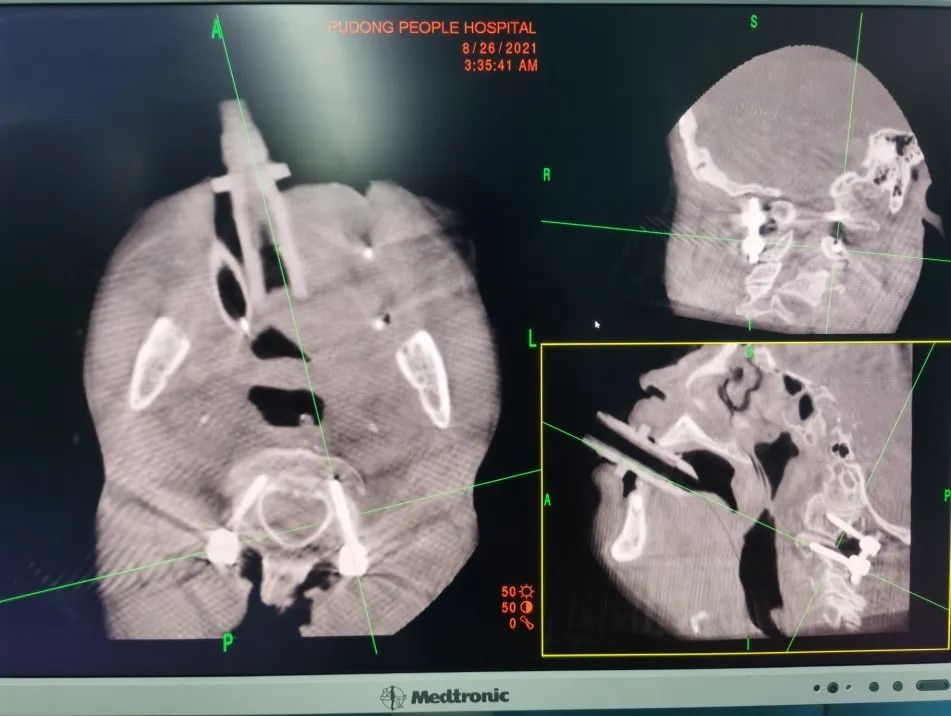

手术过程:经鼻插管全身麻醉后,在持续颅骨牵引状态下完成体位摆放、寰枢椎复位操作。在摆放过程中利用Mayfield架固定头颈,胶带将上肢固定于身体两侧,术中O-arm确认枢椎齿状突及寰枢椎得到有效复位。

患者颈后切口示意图、O-arm应用术中显露枕骨大孔周缘、寰椎后弓、枢椎棘突及椎板、寰枢椎侧块,C4棘突上放置示踪器,术中O-arm自动扫描获取寰、枢椎重建影像并传输至导航系统自动注册。

然后在导航图像引导下,在寰、枢椎选取最佳进钉点和进钉角度植入椎弓根螺钉。

内固定植入术后O-arm扫描重建图像显示C1-2椎弓根钉置钉位置精确随后弯棒固定、锁紧螺钉尾帽。